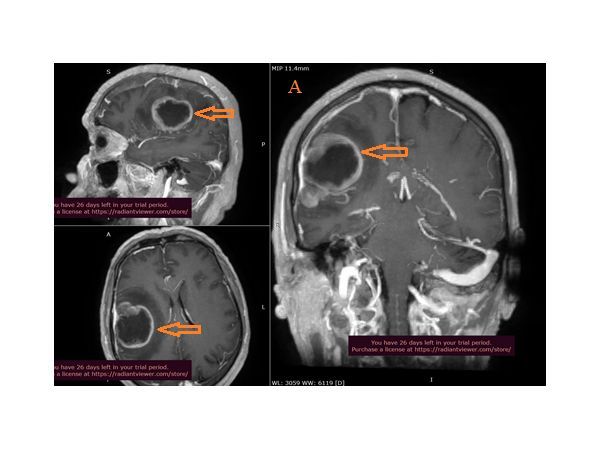

- МРТ головного мозга с контрастным усилением — объёмное образование в правых лобной и теменной долях, отдельно лежащий метастаз в правой теменной доле, срединные структуры смещены в сторону;

Пациенту провели операцию, в ходе которой удалили опухоль в правой лобно-теменной области головного мозга с помощью микрохирургической техники, интраоперационного микроскопа и станции планирования Brainlab, которая позволяет удалить новообразование без последующих неврологических осложнений.